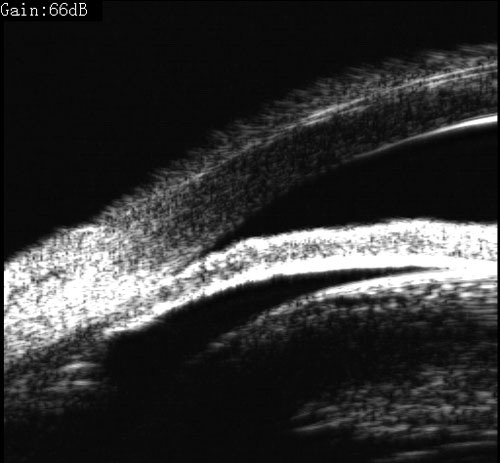

青光眼合并白内障